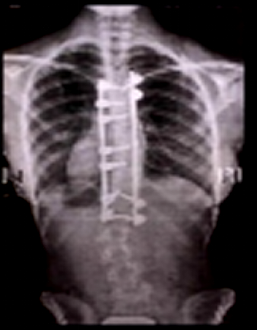

理疗颈椎病、胸椎病背部疼痛、僵硬、怕凉,上

593x600 - 52KB - JPEG